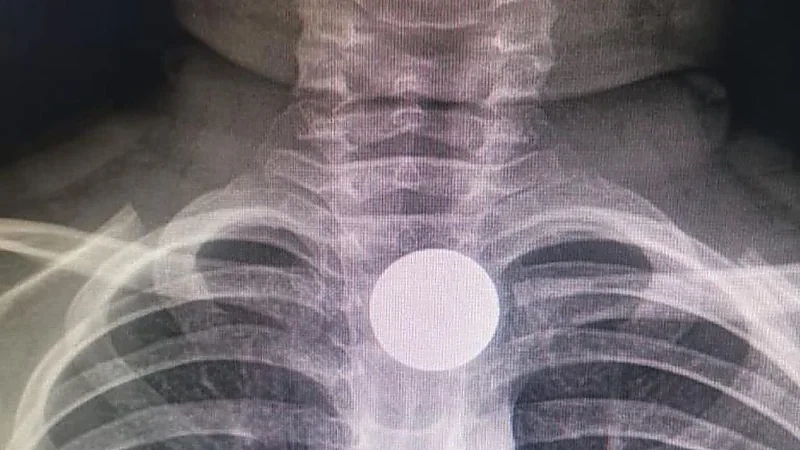

تفاصيل انقاذ حياة طفل في الخفجي ابتلع قطعة معدنية

الدمام

منذ 4 سنة

0

1776